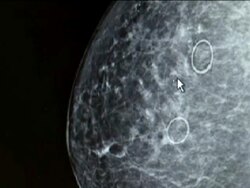

Mammogram X-Ray

Mammogram X-Ray on May 16, 2011 in Dallas, Texas (Footage by Tribune Broadcasting/Getty Images)